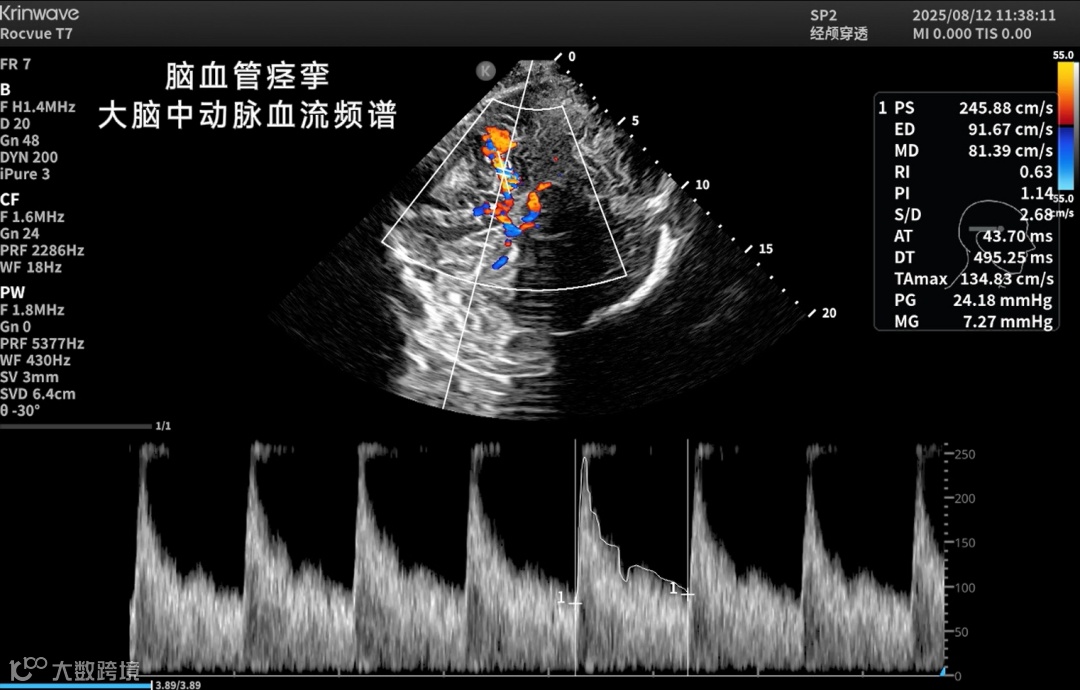

颅脑一直是超声成像的难题——

颅骨厚、衰减强、反射乱,声能传输率不足10%。

让超声在颅脑领域真正“看得见、看得清”。

● 脑卒中防治

实现院前识别、院中动态监测与干预评估;